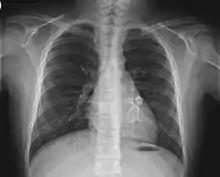

Heart complications are the most important aspect of Kawasaki disease, which is the leading cause of heart disease acquired in childhood in the United States and Japan.[31] In developed nations, it appears to have replaced acute rheumatic fever as the most common cause of acquired heart disease in children.[15] Coronary artery aneurysms occur as a sequela of the vasculitis in 20–25% of untreated children.[52] It is first detected at a mean of 10 days of illness and the peak frequency of coronary artery dilation or aneurysms occurs within four weeks of onset.[48] Aneurysms are classified into small (internal diameter of vessel wall <5 mm), medium (diameter ranging from 5–8 mm), and giant (diameter > 8 mm).[31] Saccular and fusiform aneurysms usually develop between 18 and 25 days after the onset of illness.[15]

Even when treated with high-dose IVIG regimens within the first 10 days of illness, 5% of children with Kawasaki disease develop at the least transient coronary artery dilation and 1% develop giant aneurysms.[53][54][55] Death can occur either due to myocardial infarction secondary to blood clot formation in a coronary artery aneurysm or to rupture of a large coronary artery aneurysm. Death is most common two to 12 weeks after the onset of illness.[15]

Many risk factors predicting coronary artery aneurysms have been identified,[21] including persistent fever after IVIG therapy,[56][57] low hemoglobin concentrations, low albumin concentrations, high white-blood-cell count, high band count, high CRP concentrations, male sex, and age less than one year.[58] Coronary artery lesions resulting from Kawasaki disease change dynamically with time.[4] Resolution one to two years after the onset of the disease has been observed in half of vessels with coronary aneurysms.[59][60] Narrowing of the coronary artery, which occurs as a result of the healing process of the vessel wall, often leads to significant obstruction of the blood vessel and the heart not receiving enough blood and oxygen.[59] This can eventually lead to heart muscle tissue death, i.e., myocardial infarction (MI).[59]

MI caused by thrombotic occlusion in an aneurysmal, stenotic, or both aneurysmal and stenotic coronary artery is the main cause of death from Kawasaki disease.[61] The highest risk of MI occurs in the first year after the onset of the disease.[61] MI in children presents with different symptoms from those in adults. The main symptoms were shock, unrest, vomiting, and abdominal pain; chest pain was most common in older children.[61] Most of these children had the attack occurring during sleep or at rest, and around one-third of attacks were asymptomatic.[15]

Valvular insufficiencies, particularly of mitral or tricuspid valves, are often observed in the acute phase of Kawasaki disease due to inflammation of the heart valve or inflammation of the heart muscle-induced myocardial dysfunction, regardless of coronary involvement.[59] These lesions mostly disappear with the resolution of acute illness,[62] but a very small group of the lesions persist and progress.[63] There is also late-onset aortic or mitral insufficiency caused by thickening or deformation of fibrosed valves, with the timing ranging from several months to years after the onset of Kawasaki disease.[64] Some of these lesions require valve replacement.[65]